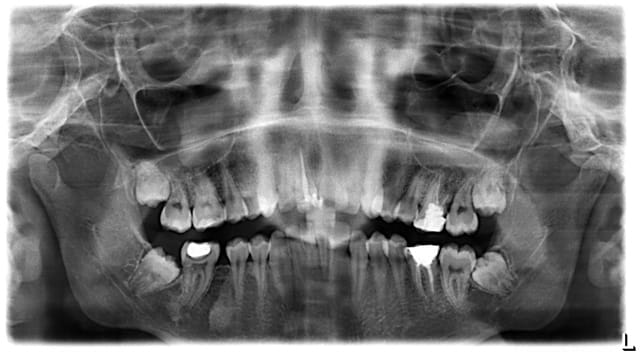

voici opour info les pano avant tt et en cours. la 36 a ete extraite et je m'imaginais que les 37 47 sortiraient seules...

Messafah s 19860715 70194472 6 fl9kqr - Eugenol

Messafah s 19860715 70162568 3 b5qan8 - Eugenol

Il me semble que la 46 est manquante, et que c'est la 48 qui est incluse...

Il semble y avoir une lésion sous la 47...